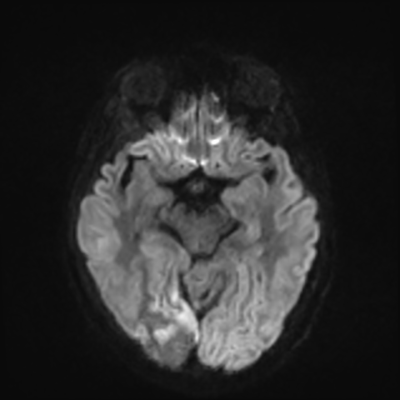

MRI brain (DWI)

MRI brain (DWI) 3/24 3/24

You can clearly see diffuse cortical and basal ganglia diffusion restriction, and that of his deep cerebellar nuclei as well. The right occipital lobe abnormalities are a little more prominent, but then you remember that he is known to have had a right occipital stroke weeks ago.

In reviewing his data, you know that he doesn't have any of the strong predictors of a poor neurologic prognosis. However, based on these findings on MRI, along with the absent reactivity on cEEG, you are able to tell the primary team and the patient's family that he is likely to have a poor prognosis, based on these multiple moderate predictors. Recovery is not completely impossible-- there is more uncertainty with this prognostication than if we were able to get SSEPs-- but you're very worried about his outlook and that any potential recovery would require a very protracted rehabilitation period. Given his high cervical cord injury level, tracheostomy would be required anyway. So, it comes down to whether his family thinks he'd want to pursue these aggressive measures.